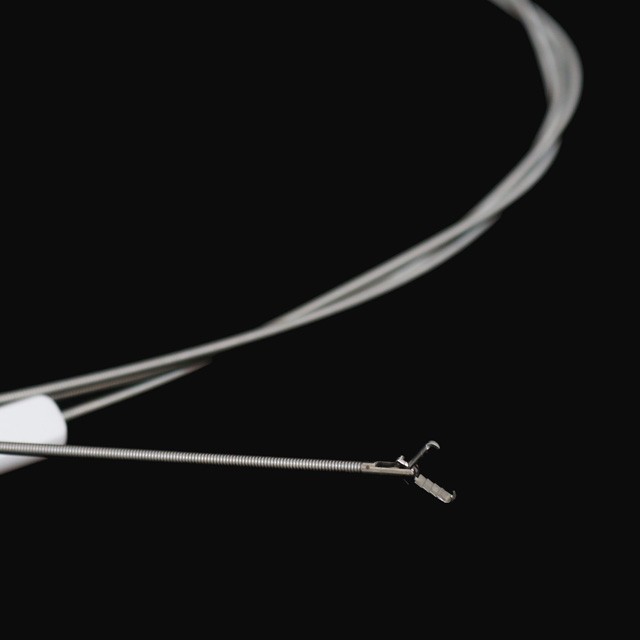

جوڙ جو قسم

fg -28 ڪي 1 |

2.3 |

2.8 کان وڌيڪ يا برابر آهي |

1600 |

نه |

اليگيٽر |

fg -28 K3 |

2.3 |

2.8 کان وڌيڪ يا برابر آهي |

1600 |

نه |

چوٿون دانت سان گڏ |

fg -28 K-A4 |

2.3 |

2.8 کان وڌيڪ يا برابر آهي |

1600 |

نه |

ليکڪو |

fg -28 K-A5 |

2.3 |

2.8 کان وڌيڪ يا برابر آهي |

1600 |

ها |

اليگيٽر |

fg -28 K-A7 |

2.3 |

2.8 کان وڌيڪ يا برابر آهي |

1600 |

ها |

چوٿون دانت سان گڏ |

fg -28 ڪي 8 |

2.3 |

2.8 کان وڌيڪ يا برابر آهي |

1600 |

ها |

ليکڪو |